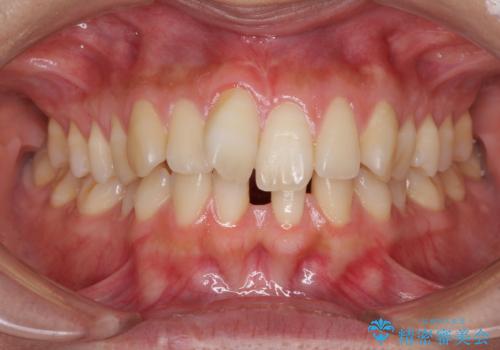

- 下顎前歯の欠損により隙間ができていることを気にして来院された患者様です。

下顎前歯が2歯欠損しており、スペースになっており、上顎は叢生歯列となってしました。

奥歯の咬み合わせを考えると、理想的には2歯、最低でも1歯は下顎前歯の欠損部にインプラントやブリッジにより歯数を増やす必要がありました。